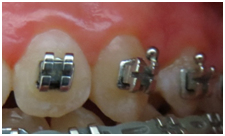

From a total of 12 screened participants, lesions .The patients were reexamined at three and six months. Nyvad Scores 1:112 faces (83,6%); 2=14 faces (10,4%); 3 =6 faces (4,5%); 5 =2 faces (1,5%). The active white spots, were more frequent in score 1, when compared to scores 2, 3 and 5, significant at 1%. Score 2, had significative differences towards score 5. The active white spots, were more frequent in score 1, when compared to scores 2, 3 and 5, significant at 1%. Score 2, had significative differences towards score 5 (Table 1). After three month, from the 134 white spot lesions, the majority of them inactivated 130 (97,01%), became inactive, while 4 remain active. The scores achieved after three month remain stable till one year evaluation (Table 2). Figure 1 & 2 shows clinical differences before and after the use of a raging on 4 week uses consecutively tooth mousse in orthodontic treatment, during treatment (Figure 3A & 3B), and after orthodontic treatment (Figure 4A & 4B).

Figure 3B Lucas after three month 4 weeks TM.

Figure 4B Angelica one year after 4 weeks tooth mousse.